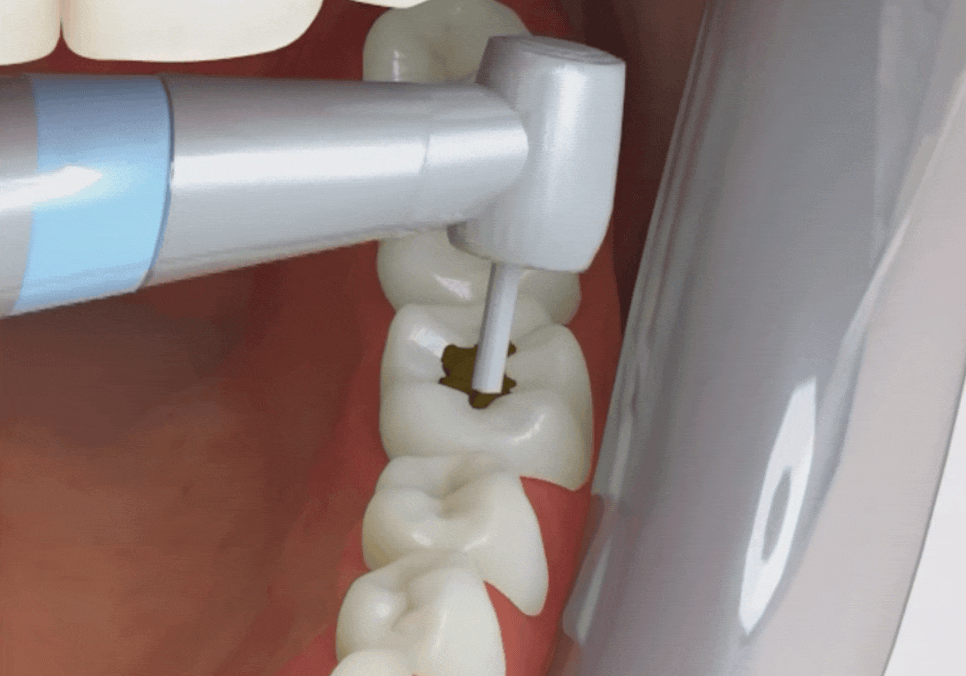

레진은 한 번에 툭 채워 넣으면 편하겠지만,

그러면 미세한 틈이 생기기 쉬워요.

조금 힘들더라도 얇게 층을 나누어 쌓고 굳히는

'적층법'을 고집하는 이유입니다.

그래야 치아와 빈틈없이 밀착되고

자연스러운 투명감도 살아나거든요.

치아를 거의 깎지 않고

내 치아를 최대한 살려드리고 싶은

제 마음이기도 합니다. ^^